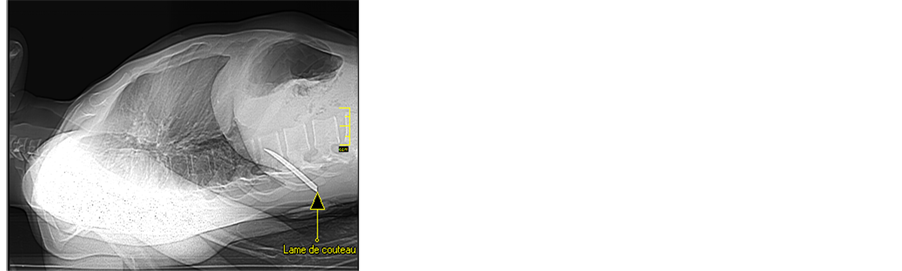

In the emergency Ward, sterile dressing of the wound was done, an intravenous line was inserted, blood samples were collected, and antibiotics were started along with high dose methylprednisolone (Houde laboratories, Paris, France) protocol (30 mg/kg IV infusion in one hour and then 5.4 mg/kg given over 23 hours). After that, a computed tomography (CT, Toshiba, Tokyo, Japan) scan of thoracolumbar spine was done. It revealed: vertebral and spinal cord injury with an incarcerated 8 cm broken knife blade, complete spinal cord transection at T11 - T12 level, and hyper intense hematoma along the wound tract (Figure 1). The patient was operated as an emergency under general anesthesia with endotracheal intubation. A midline posterior approach extending between T9 and T12 levels was performed. Opening of the superficial dorsal aponeurosis immediately revealed the incarcerated knife blade. Para spinal muscles were severed subperiostly, spinous processes removed and T11 - T12 laminectomy was done. It was noticed that the knife had broken the T12 spinous process, torn the spinal dura, transected the spinal cord and got stuck into the inferior part of T11 vertebral body. The incarcerated broken knife blade was gently pulled out with a rongeur. This revealed the spinal cord transection with a compressive hematoma at the injury site. The hematoma was removed with smooth suction and spinal cord wound washed with warm normal saline. Dura opening was sutured with 3/0 nylon sutures and the wound closed in layers (Figure 2). The immediate postoperative period was marked by a rapid recovery of motility and sensation so that at two weeks after surgery, muscle strength was at least 3 in all muscle groups ensuring motility of lower limbs till the legs. Nevertheless, motility of the feet remained null (level L5 and below). The patient was discharged from hospital on day 14 after surgery for a rehabilitation center. Thirty two months after surgery, patient’s neurological status was unchanged although he mentioned a slight improvement in sphincter disturbances.

Figure 1. Spine computed tomography scans. (a) Scoot view showing the incarcerated broken knife blade (arrow); (b) Hypo intensity due to artifact from metallic foreign body (arrow); (c) Axial view showing blood clot within spinal cord (upward arrow) and hypo intense artifact from the knife blade (downward arrow); (d) Hyper intensity due to hematoma along the wound tract (arrows).